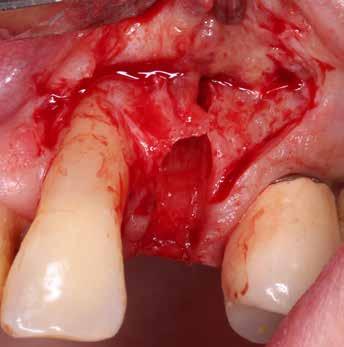

A socket-shield technika lényege az azonnali implantációt megelőző részleges fogeltávolítás. Dekoronálást követően a megmaradt gyökér több darabban kerül eltávolításra, azonban a bukkális

4. a–c képek: A fog dekoronálása.

5. a–e képek: Részleges extrakció.

igen vékony (0,5-1,5 mm), bukkális köteges csont (bundle bone) lebomlásához vezetne a periodontális ligamentumok felől megszűnő vérellátás miatt.

A teljes palatinális gyökérrészlet és az apex eltávolítása után a megmaradt bukkális dentinfalat kb. 0,75-1 mm-re elvékonyítva, továbbá a koronális dentinszélt csontszintig preparálva készül el a megmaradó foggyökér-részlet. Az összes endodontális maradvány (pulpa, illetve esetleges gyökértömés), valamint az apex teljes mértékű eltávolítása kulcsfontosságú az implantátum sikeres osszeointegrációja szempontjából.

A részleges extrakció befejezése után következhet az implantátumágy preparálása a gyártó utasításai szerint (6.

falat mint „pajzsot”, meg kell őrizni, ezzel megelőzhető a bukkális csontfal egyébként fiziológiás reszorpciója (4. és 5. kép). A sebészi technika különös körültekintést követel meg, nehogy a bukkális „gyökérpajzs” megmozduljon, ezzel a bukkális oldalon megmaradt periodontális ligamentumok sérülését kockáztatnánk, amely az esetenként